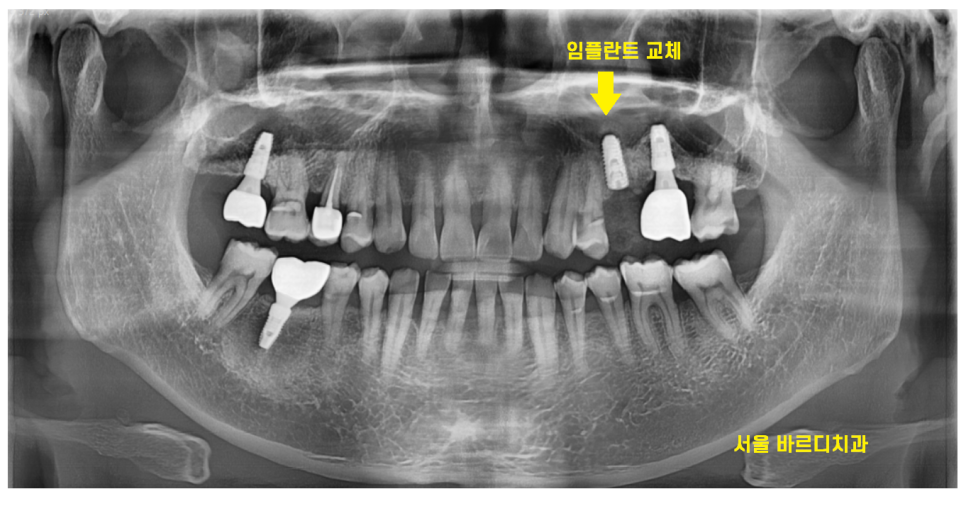

24.03.08

뼈이식 한 부분이 잘 만들어지고 있는지

주기적으로 오셔서 확인

24.04.13

뼈가 잘 만들어졌을 때

길동 치과에서 임플란트 수술 진행해드렸습니다.

기존 수명이 다한 임플란트를 제거

교체 해준 셈이죠.